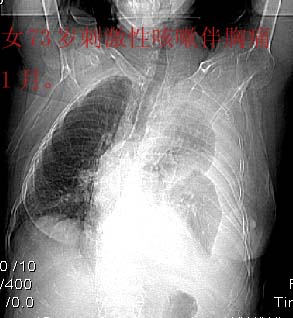

标题: CT4907:[原创]胸部平扫,请讨论!谢谢!!

考虑:左侧大量胸腔积液伴下叶压迫性且不张。

中央型肺癌,下叶不张,胸水

左侧大量胸腔积液伴下叶压迫性且不张,心包积液,左下叶支气管变窄,建议增强扫描,排除占位

左侧大量胸腔积液伴左下肺不张,左侧支气管狭窄,左舌段有膨胀感,中央型肺癌待排,心包有少量液体。肝顶部低密度影,需进一步检查

左侧大量胸腔积液伴左下肺不张,左侧支气管狭窄,左舌段有膨胀感,中央型肺癌待排,心包有少量液体

左侧大量胸腔积液,左下叶受压不张,纵隔向右侧轻移位,虽未见明显骨质破坏,但临床有刺激性咳嗽、胸疼等都支持非善类病变,应穿刺抽液细胞学检查,考虑右肺癌并胸膜转移。肝顶部似有低密度影,可进一步检查,排除转移灶。

患者以抽胸水到上级医院作细胞学检查,肝右顶部的确是{患者以作b超:囊性低密度区,考虑囊肿?}病灶。我的初步意见是考虑是左侧中央型肺癌。

1、高度怀疑:左肺中央型肺癌伴肺不张、胸水;

2、肝上病灶暂考虑囊肿。

3、心包内脂肪影清晰,未见积液。

左侧大量胸腔积液伴左下肺不张,左侧支气管狭窄,左舌段有膨胀感,中央型肺癌待排.